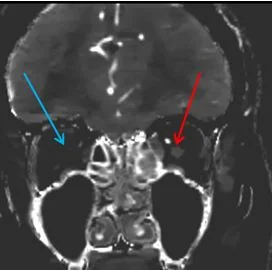

Iodine map: Absent uptake in right optic nerve (blue arrow). The left optic nerve shows good iodine uptake (red arrow).

91 year old female presents with sudden painless loss of vision in the right eye. Fundoscopic exam consistent with central retinal artery occlusion. Head CT showed chronic left medial occipital infarct, and changes of small vessel disease. CT angiogram performed as part of stroke workup showed left PCA stenosis, ophthalmic arteries were patent.

Dr Ben Hoffman turns on spectral. And lo and behold, the right optic nerve shows no iodine uptake. To the best of my knowledge, lack of perfusion on CT in CRAO has not been described before.